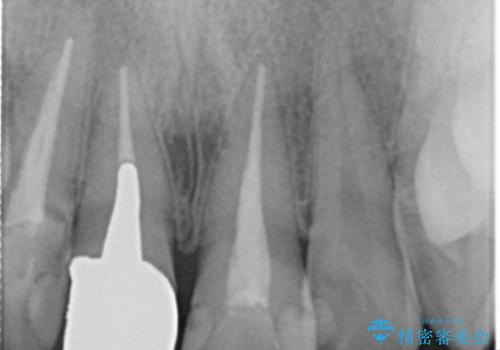

左の前歯は樹脂での治療がされていてう蝕が再発していたので全て取り除き、再根管治療(保険)を行いました。

根管治療をした後、樹脂で埋めるだけで治療を終えてしまうと歯質と樹脂の隙間から細菌が入り込み、う蝕や根の感染の再発に繋がります。

適合の良い被せ物を入れることで再発リスクが低くなります。